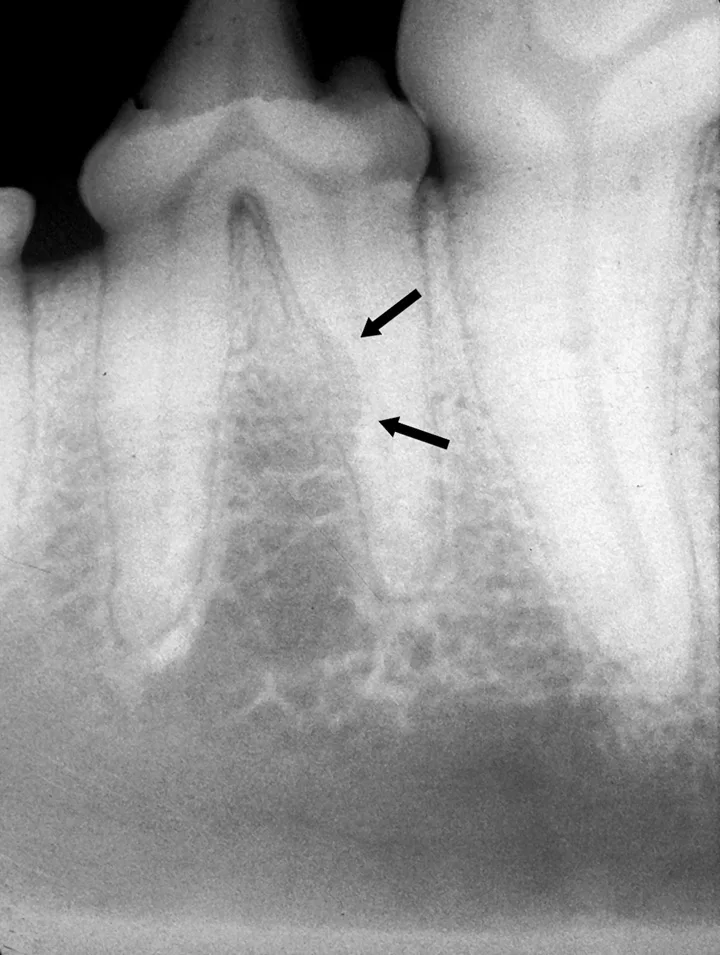

Intraoral radiograph of the rostral mandibles revealing advanced external resorption affecting both canine teeth

Resorption of the right maxillary canine root in a 3-year-old English bulldog.